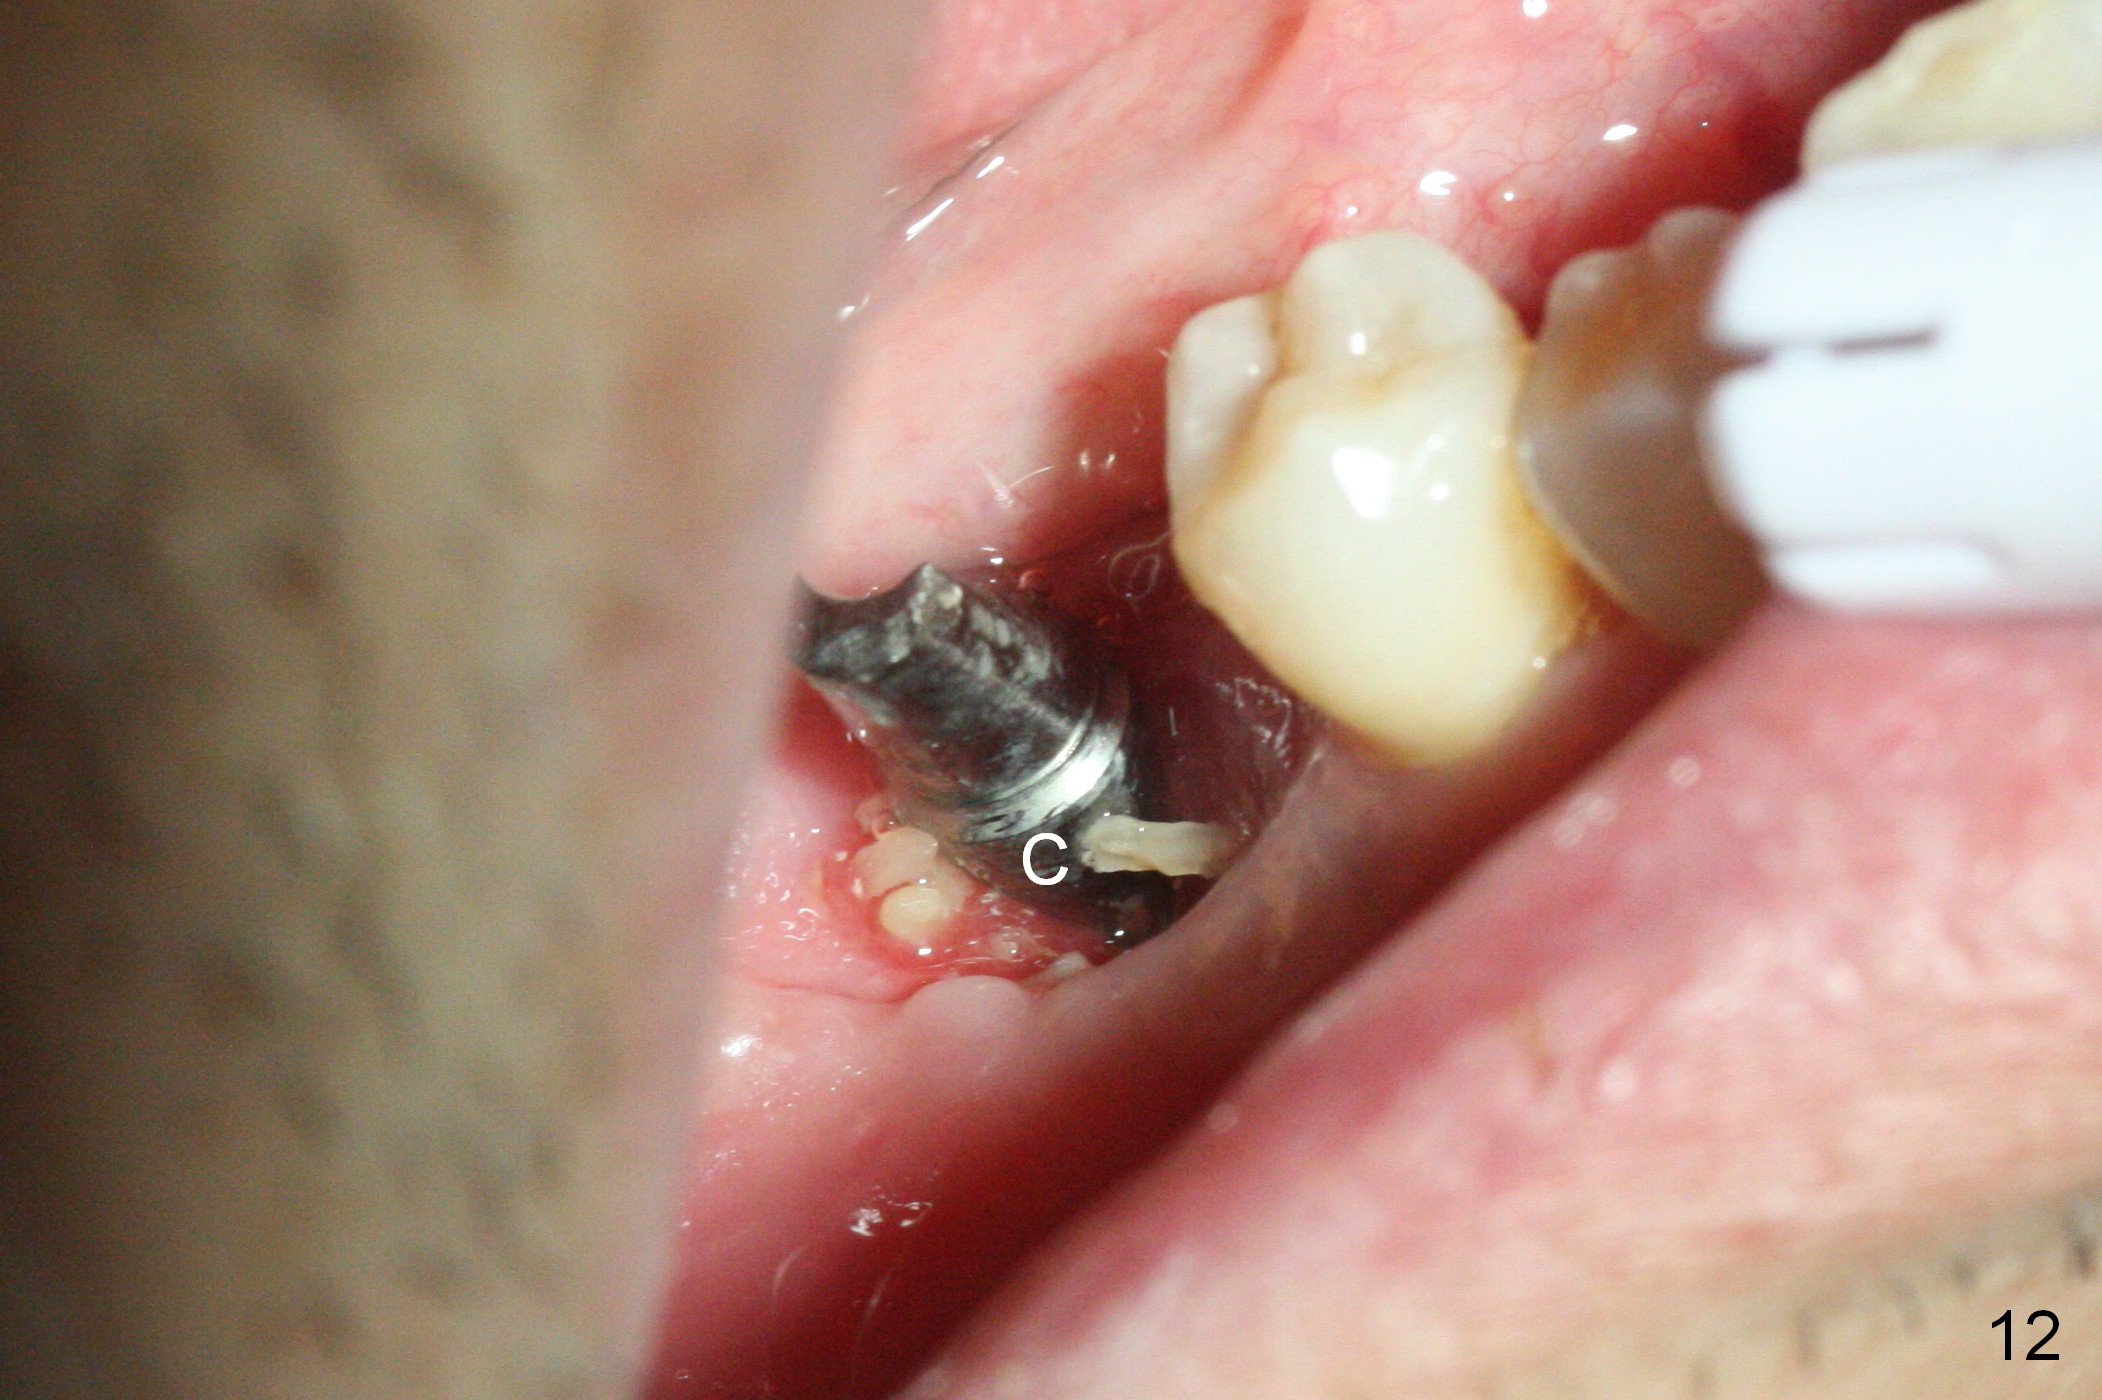

The non-resorbable membrane stays in place 1 month postop (Fig.11 N). When it is removed, the buccal aspect of the cuff of the angled abutment is not covered by bone graft or granulation tissue (Fig.12 C). In fact, the membrane does not hold the bone graft in place as effectively as a provisional. The space is filled with a piece of gauze (Fig.13) while the abutment is reduced for provisional and MO composite at #31 is placed. Before seating the provisional (Fig.14 P), a piece of collagen plug is inserted into the space (*) after removal of the gauze.